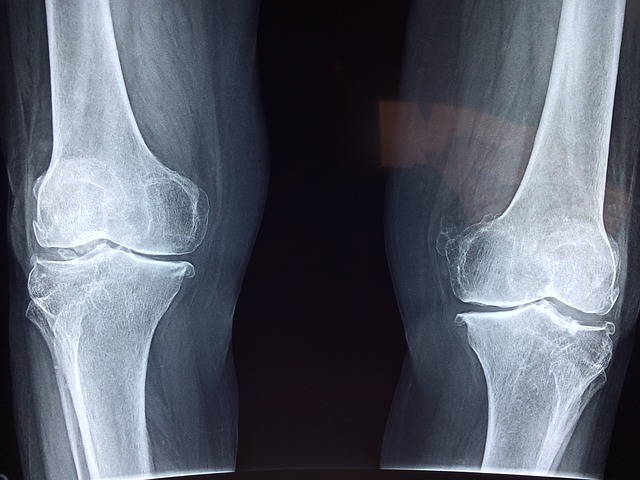

우리의 관절은 나이가 들수록 몸이 퇴행성 변화를 거치게 되고 매끈하던 연골이 거칠어지고 윤활 성분도 줄어들게 됩니다.

무릎 연골이 무너지는 퇴행성 관절염 이후 목 디스크, 허리 디스크 등의 증상과 염증 수치가 올라가 우리의 건강은 점점 악화되는 과정을 겪게 될 수도 있습니다.

1. 뼈, 피부, 장기 같은 모든 부분에서 연골 세포를 건강하게 유지하고 연골 손상을 막아 관절염을 예방하는데 도움을 줍니다.

4. 뼈조직의 연골량 보호에도 효과적으로 도움을 줍니다.